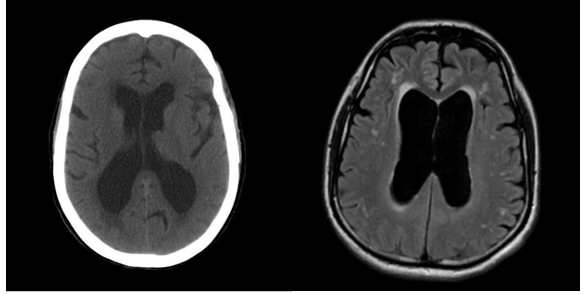

根据临床表现,对于怀疑有脑功能退化的患者,医生会安排影像学检查,包括电脑扫描和磁力共振,发现是否有结构异常,脑萎缩和脑积水等情况。当脑神经退化时,脑萎缩同时脑脊液体积相对增加,如果脑脊液增加不成比例,尤其对脑室产生压力和脑水肿迹象,就需要进一步诊断,排除压力异常的脑积水。这时通常需要做腰椎穿刺的诊断程序,测量硬膜下压力并放出脑脊液,当低压可以改善步态和认知反应,就可以考虑进行脑室腹腔分流手术治疗,使脑脊液循环回复正常。